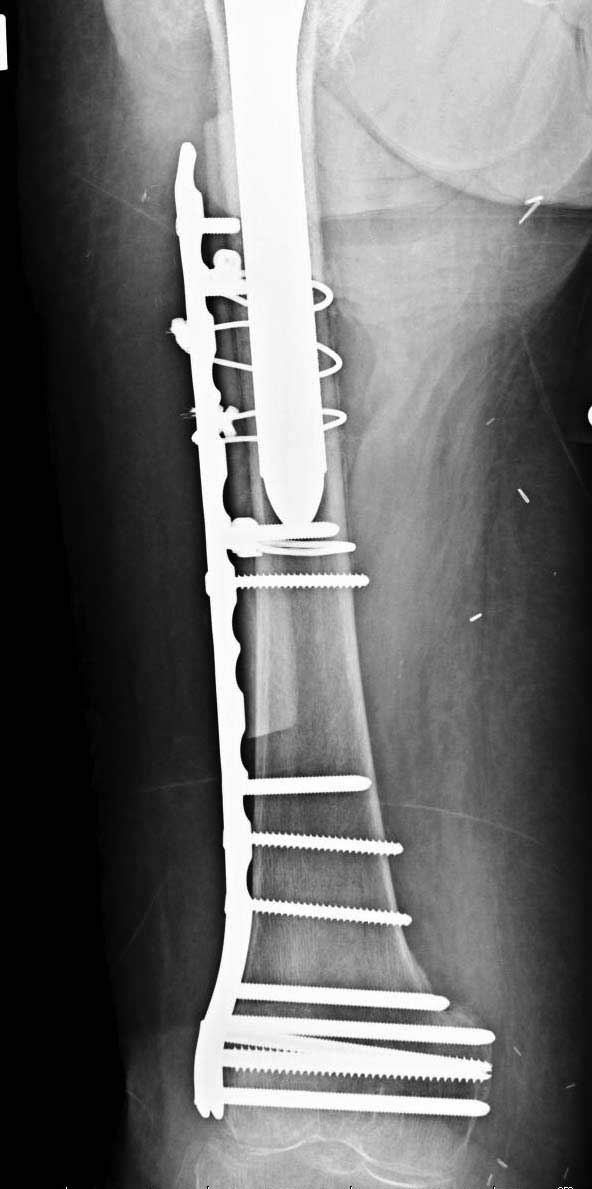

Обычно после чрезвертельных переломов, за исключением молодых, у пожилых остается нестабильность при движении. Часто падают и после 3х мес. в результате падения обнаружен перипротезный перелом (22-23), который зафиксирован Синтез пластиной.

Имя     : 26 periprosthetic fx 2.jpg

Тип     : image/jpg

Размер  : 51985 байтов

Описание: отсутствует

Url     : http://weborto.net:8080/pipermail/ortho/attachments/20120509/52aada75/attachment-0048.jpg